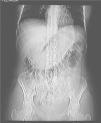

Presentamos una paciente de 16 años de edad que consulta en su Centro de Salud, por cuadro de dolor abdominal difuso, vómitos alimenticios de 2 días de evolución, pérdida de peso y deposiciones líquidas 2 días antes. La madre, que la acompaña, refiere alteraciones emocionales y episodios depresivos que han precisado tratamiento psiquiátrico ese mismo año. A la exploración se palpa una masa abdominal en epigastrio, que sobresale al reborde costal, móvil, dolorosa y de consistencia dura. Se envía al hospital para realizar las exploraciones complementarias oportunas. Se practica radiografía en vacío de abdomen (fig. 1) en la que aparece un aumento de densidad en epigastrio que forma una especie de molde de la cavidad gástrica y desplaza las asas intestinales. En la ecografía posterior se objetiva formación hiperecogénica con sombra acústica posterior en área gástrica, adyacente a hígado y vesícula biliar (fig. 2). Durante todo el proceso la chica mantiene la cabeza cubierta con una gorra y al retirársela se aprecian áreas irregulares de alopecia. Se interroga a la paciente sobre la ingesta de cabello, que niega inicialmente en presencia de la madre y que posteriormente reconoce en ausencia de ésta. Ante la evidencia de tricotilomanía y tricofagia se realiza tomografía computarizada (TC) abdominal con administración de contraste oral e intravenoso y cortes de 7 mm de grosor, para confirmar la sospecha de bezoar gástrico, demostrándose los hallazgos típicos que proporciona esta técnica (fig. 3). La paciente fue intervenida quirúrgicamente, realizándose laparotomía y gastrotomía anterior amplia, extracción del tricobezoar y comprobación de ausencia de progresión de la masa hacia el duodeno. La evolución posterior fue satisfactoria y actualmente sigue controlada en la consulta de psiquiatría.

Figura 1. Radiografía abdominal convencional. Se aprecia aumento de densidad que dibuja el molde gástrico, con alguna burbuja aérea y desplazamiento de estructuras adyacentes (colon).

En lo referente a las pruebas complementarias, la radiología convencional no proporciona una imagen característica. Puede objetivarse una aumento de densidad con sensación de masa y pequeñas burbujas aéreas radiolucentes, que se desplaza con los cambios de posición, y que puede confundirse con la presencia de heces en el colon o incluso con abscesos o bien, como en el caso que presentamos (fig. 1), que rellene completamente la cavidad gástrica produciendo un molde evidente en el estudio radiológico convencional y desplazamiento de estructuras adyacentes. En ecografía la presencia de una masa intraluminal con un marcado anillo hiperecogénico en la superficie y una sombra acústica posterior es sugerente de bezoar12. La TC es la técnica radiológica más específica, determina una apariencia característica como una masa intraluminal, bien definida, de baja densidad, con burbujas de aire o restos de contraste. Permite además determinar sus dimensiones, su posible extensión hacia el intestino y la existencia de bezoares múltiples adicionales. Es la técnica más útil para determinar la presencia de posibles complicaciones, por lo tanto puede considerarse la técnica de elección de diagnóstico prequirúrgico8,13.